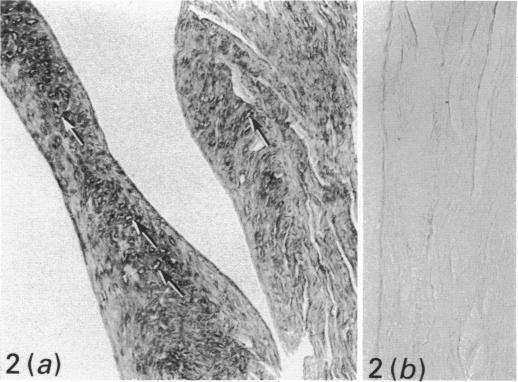

The localisation and ontogenic expression of heart fatty acid binding protein (H-FABP) were immunochemically examined in the entire body of the rat. In muscles, H-FABP immunoreactivity was observed not only in cardiac muscle cells but also in red skeletal muscles, where gold particles indicating the immunoreaction sites are distributed evenly in the sarcoplasm except for the interior of membranous organelles. In the urogenital system, the immunoreactivity was preferentially demonstrated in the distal tubular epithelial cells in the kidney, and in the superficial epithelial cells in the urinary bladder. The H-FABP immunoreactivity was further found in cells characterised by numerous lipid droplets, such as interstitial cells of the theca interna in the ovary and those of Leydig in the testis, and cell Element III in the placenta. In the digestive system, parietal cells in the stomach and pancreatic beta-cells were immunoreactive to H-FABP. In addition, capillary endothelial cells were immunostained in the cardiac and red skeletal muscles, the exocrine pancreas, digestive tract and thymus. From the rather wide distribution of H-FABP, it is suggested that H-FABP plays some fundamental roles in the active metabolism of fatty acids in the body. The present findings also indicate that H-FABP is a useful marker for the morphological study of interstitial cells in the ovary and testis and parietal cells in the stomach.

采用免疫化学方法对大鼠全身心脏脂肪酸结合蛋白(H-FABP)的定位及个体发生表达进行了研究。在肌肉中,不仅在心肌细胞中观察到H-FABP免疫反应性,在红色骨骼肌中也观察到了,除膜性细胞器内部外,表明免疫反应位点的金颗粒均匀分布于肌浆中。在泌尿生殖系统中,免疫反应性优先出现在肾脏远曲小管上皮细胞和膀胱表层上皮细胞中。在以大量脂滴为特征的细胞中也进一步发现了H-FABP免疫反应性,如卵巢内泡膜间质细胞、睾丸间质细胞以及胎盘的细胞成分III。在消化系统中,胃壁细胞和胰腺β细胞对H-FABP呈免疫反应性。此外,在心肌、红色骨骼肌、外分泌胰腺、消化道和胸腺的毛细血管内皮细胞也被免疫染色。鉴于H-FABP分布相当广泛,提示其在机体脂肪酸的活跃代谢中发挥着某些基本作用。本研究结果还表明,H-FABP是卵巢和睾丸间质细胞以及胃壁细胞形态学研究的有用标志物。